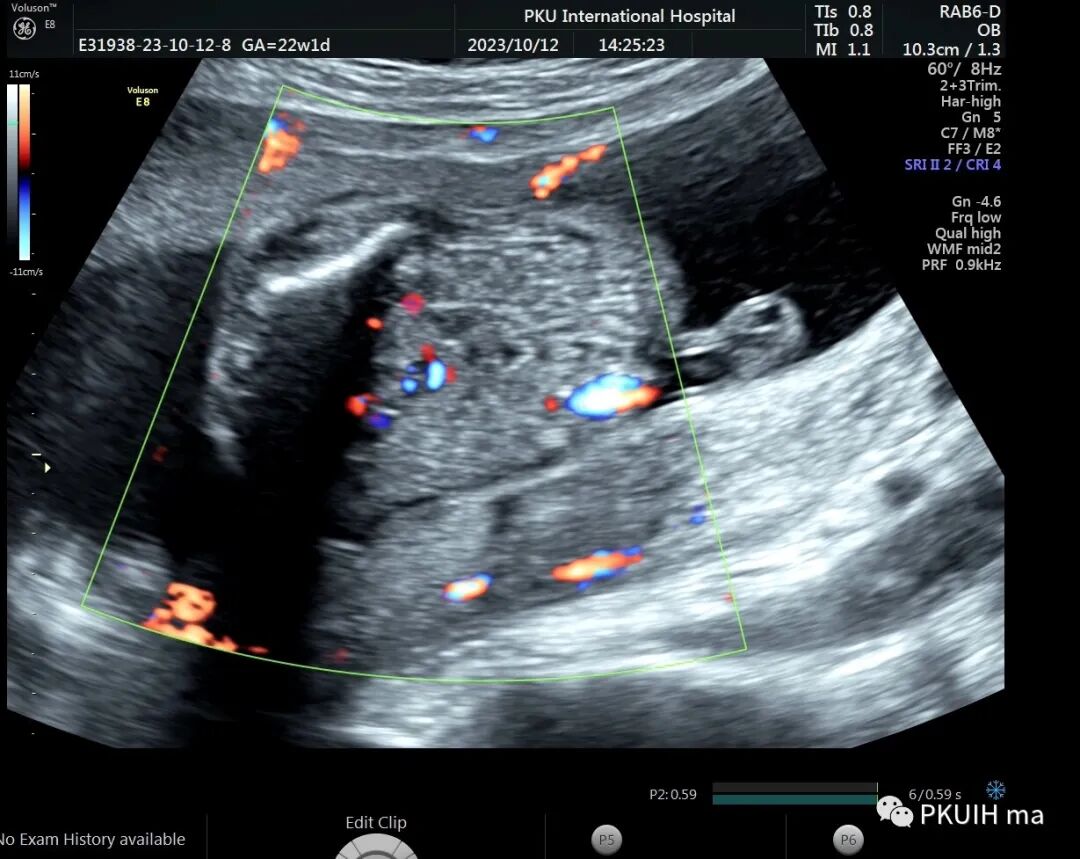

右肾大小位置正常,右肾动脉可见,左肾动脉缺如,正常的左肾区未见肾组织回声,可见肾上腺平卧。于膀胱后上方见一肾组织回声,大小约1.5x1.4x1.0cm,皮髓质分界欠清晰,血供来源于髂动脉。

异位肾较常见,发生率约1/1200,目前产前确诊并不困难。异位肾最常见的就是盆腔异位肾,占异位肾的一半以上,往往合并发育不良。血供可来源于腹主动脉或髂动脉,部分可有血管迷走。超声诊断标准:1、一侧肾区内未见肾组织回声;2、同侧的肾上腺呈平卧征;3、对侧肾可增大也可正常;4、盆腔可见一发育不良或发育正常的肾脏回声;5、可合并其他畸形,比如输卵管发育畸形或者是Vacterl综合征。